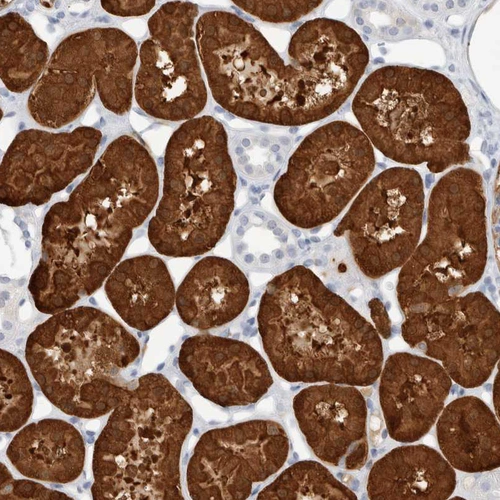

Immunohistochemical staining of human kidney shows strong cytoplasmic positivity in cells in tubules.